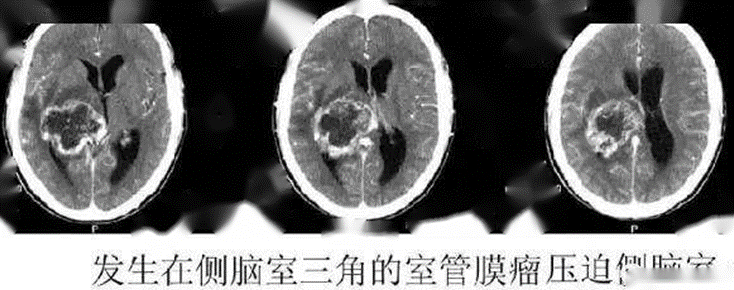

图7 不同疾病导致的脑积水